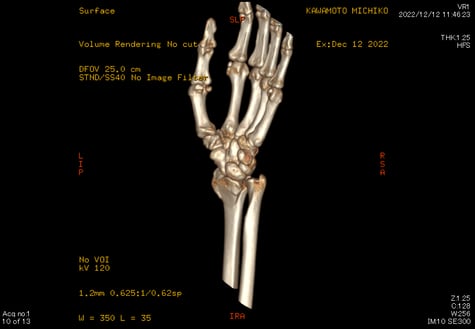

〇前腕骨遠位端骨折

当症例も手術の日程が決まっていましたがインターネットで当院を知り遠くから相談に来らました。

レントゲンとCTを見させてもらいましたが、骨折に伴い第三骨片がはみ出しています。

患者さんンは全身麻酔に抵抗があり、どうしても避けたいとのことでした。

当院で治療するとなると、当初は毎日来院していただき固定を

確認 血行障害を防ぎ 患部の清拭 超音波治療 動かせる指の

運動療法を行います。

ご住所をお聞きしたところに私の信頼する先生のご近所だったので、保存療法を希望している旨をお伝えして経過観察をお願いしました。

2か月経過したころ当院に戻られ今後のマッサージ リハビリを希望されました。

手術はしませんでしたが経過は良好です。